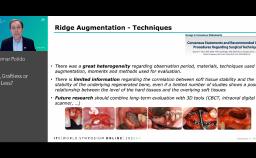

His main interests are in Computer Aided Maxillofacial and Implant Surgery, with a focus on Interdisciplinary Treatment, and in Orthognathic Surgery. He has many publications and lectures worldwide on digital tools, bone grafts, implants in the treatment of the esthetic area, complications, and the treatment of fully edentulous patients.